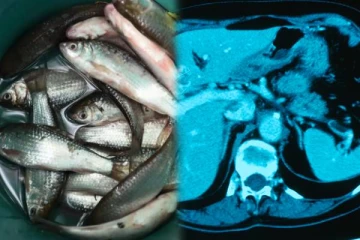

மக்களே உஷார்.. இந்த மீனை மட்டும் இப்படி சாப்பிட்டால் புற்றுநோய் உறுதி - மருத்துவர்கள் தாவல்!